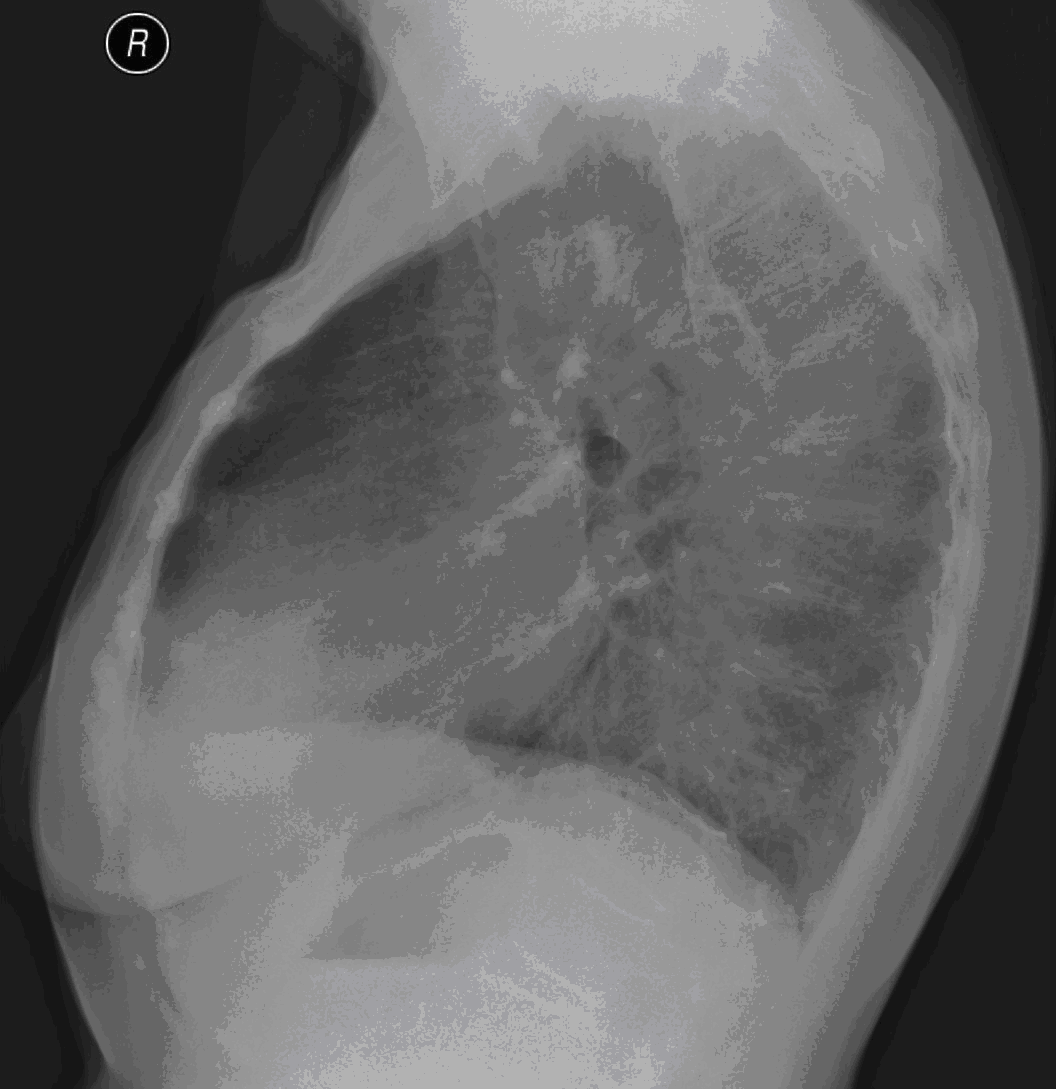

23. Pulmonary metastases, bidirectional (PA and right lateral) plain chest radiograph.

51 year old woman, endometrial carcinoma. Numerous ring shadows bilaterally in basal dominance (max. appr. 12 mm). Left pleural effusion of one finger wide.